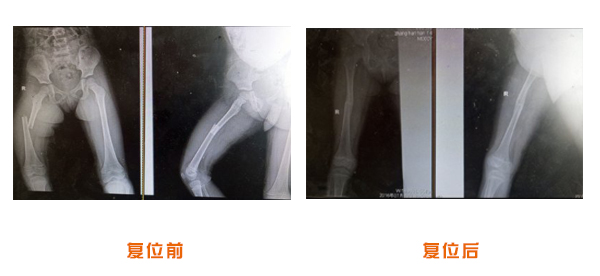

肥城市安駕莊梁氏骨科醫(yī)院是一所以梁氏手法正骨配合膏藥為特色的現(xiàn)代化專科醫(yī)院。

梁氏骨科術(shù)始創(chuàng)于清雍正年間,歷經(jīng)八代,至今已有三百年歷史。據(jù)1929年泰安縣志載“梁瑞圖先生,字增生,號蓮峰,安駕莊人,精岐黃并發(fā)明接骨,凡跌打車凡跌打車軋皮不破而碎骨者......【詳細】 |